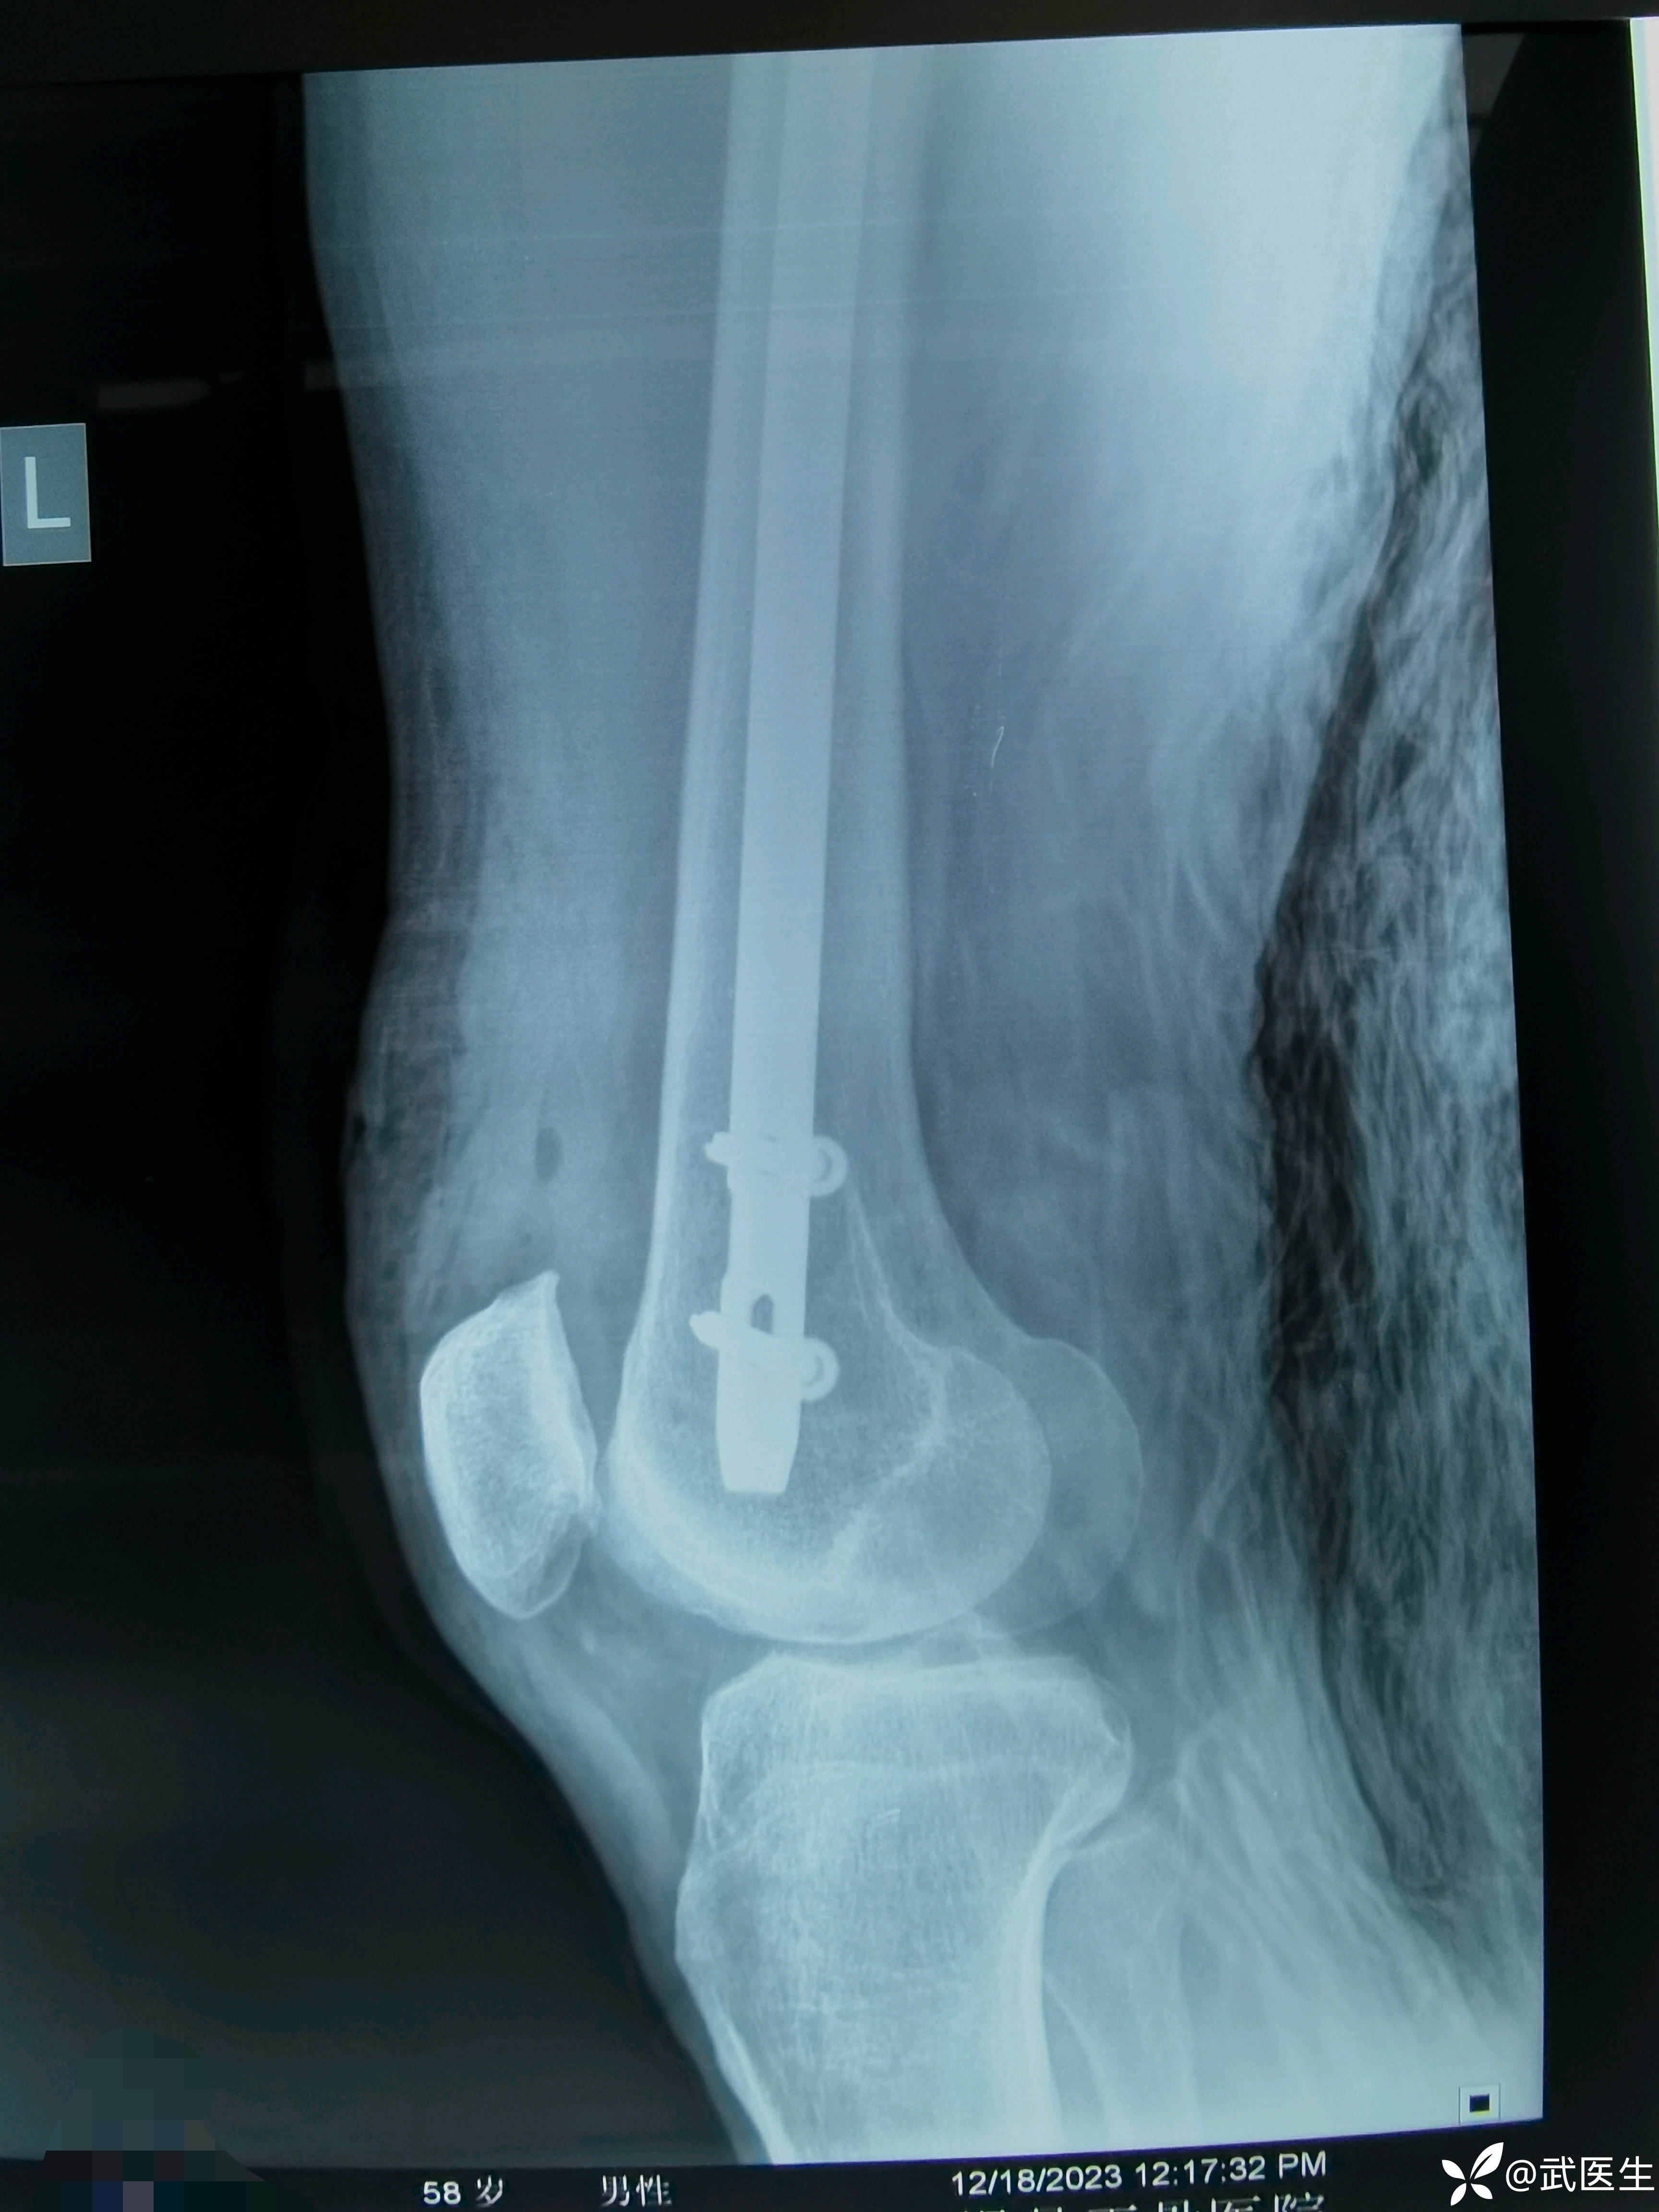

手术顺利,断端撬拨后复位能接受。